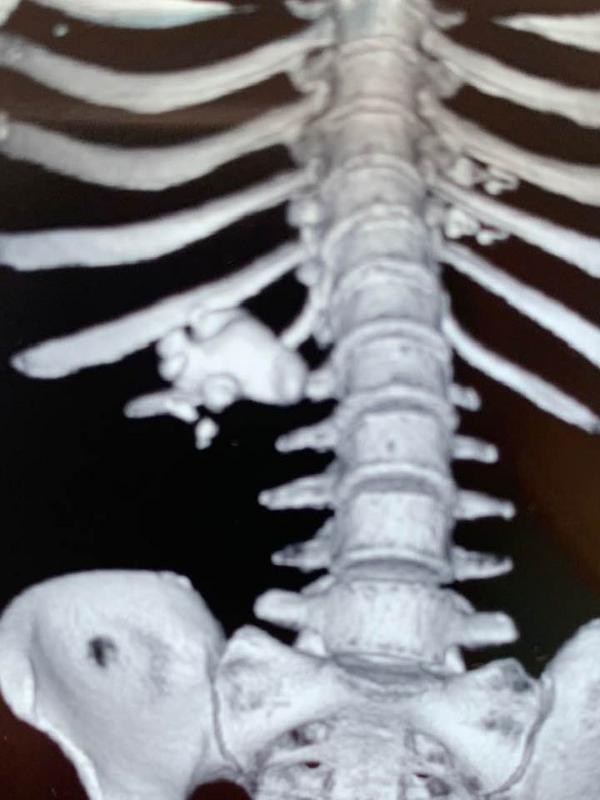

В зависимости от локализации камня, его структуры и размера командой специалистов принимается решение о методике его удаления. Самыми "тяжелыми" случаями являются так называемые коралловидные камни. Раньше они удалялись только с помощью открытой операции, после которой пациент был вынужден находиться в стационаре до двух недель.

"В арсенале нашего отделения есть самое современное оборудование (электронно-оптический преобразователь, лазерный литотриптор, фиброуретерореноскоп), которое позволяет малоинвазивно, через естественные пути или через минимальные до 5 мм проколы проводить сложнейшие операции, – рассказывает Александр Унгурян, заведующий отделением урологии городской больницы экстренной и скорой медицинской помощи, врач-уролог высшей категории, член Европейской, Американской и Украинской ассоциаций урологов. – Сейчас в случае коралловидных конкрементов мы применяем так называемую перкутанную хирургию – через прокол в области спины мы вводим в почку крошечную камеру и зонд, разрушаем камень лазером и тут же убираем его осколки. После такой операции пациент выписывается всего через 3-4 дня. Ему назначают минимум медикаментов, и он активен в тот же день".